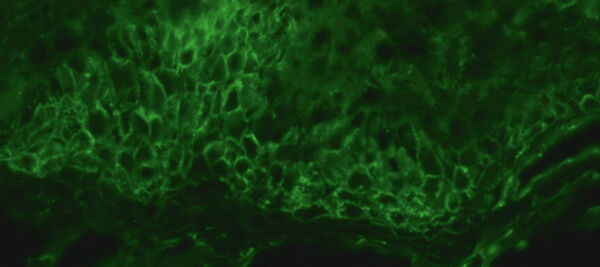

Direkte Immunfluoreszenz einer periläsionalen Hautbiopsie zeigt Ab­lagerungen von IgG an den Zell-Zell-Kontakten (interzelluläres Fluoreszenzmuster; x 250).

Häufig ist die Diagnose einer Pemphigus-Erkrankung daher bereits durch eine serologische Untersuchung möglich. Der Nachweis von Immunglobulin-Ablagerungen mit einem netzartigem Muster (Zell-Zell-Kontakte) in der Haut durch direkte Immunfluoreszenz sichert die Diagnose einer Pemphigus-Erkrankung, auch wenn hierfür noch keine spezifischen histologischen Veränderungen nachweisbar sind. Die Serumspiegel von Desmoglein-1-Ak und Desmoglein-3-Ak korrelieren gut mit der klinischen Erkrankungsaktivität. Daher eignet sich die Bestimmung dieser Autoantikörper mittels quantitativer Immunoassays (ELISA) auch als Verlaufsparameter.